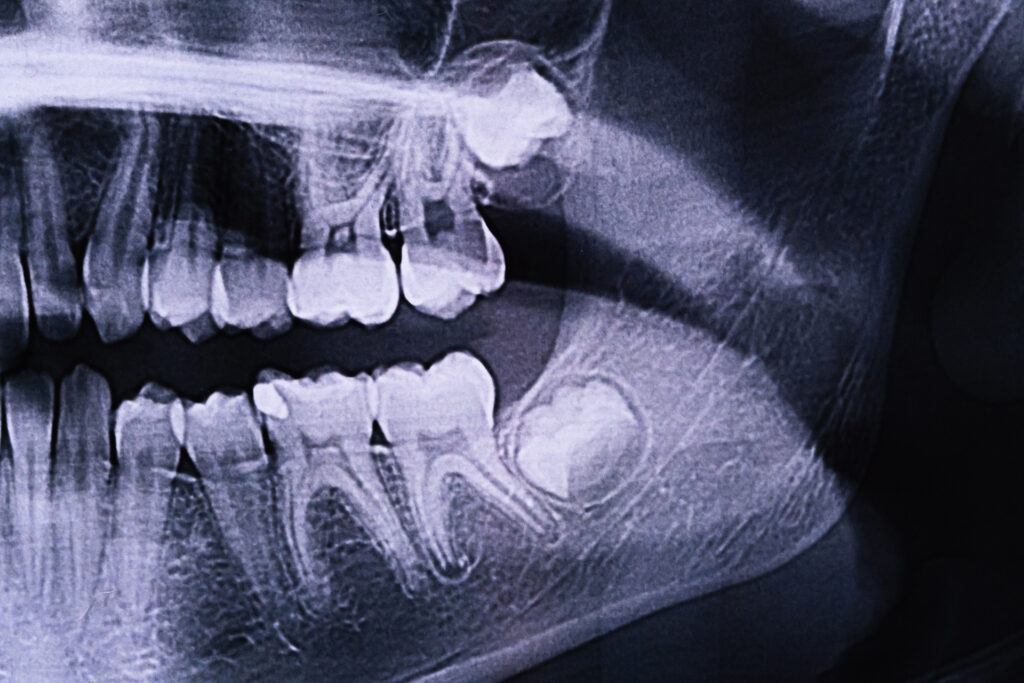

Dentists diagnose wisdom tooth decay through a combination of clinical examination and imaging. Distinguishing decay from normal eruption discomfort is especially important, since teething-related soreness can mimic the early signs of infection.

Visual inspections will reveal early signs, such as enamel breakdown, swelling or gum tenderness. Bitewing X-rays and panoramic scans will help detect cavities hidden below the gum line or inside impacted teeth, which are not visible to the naked eye. When the decay is complex or the impaction is severe, referral to an oral and maxillofacial specialist may be recommended for further evaluation.